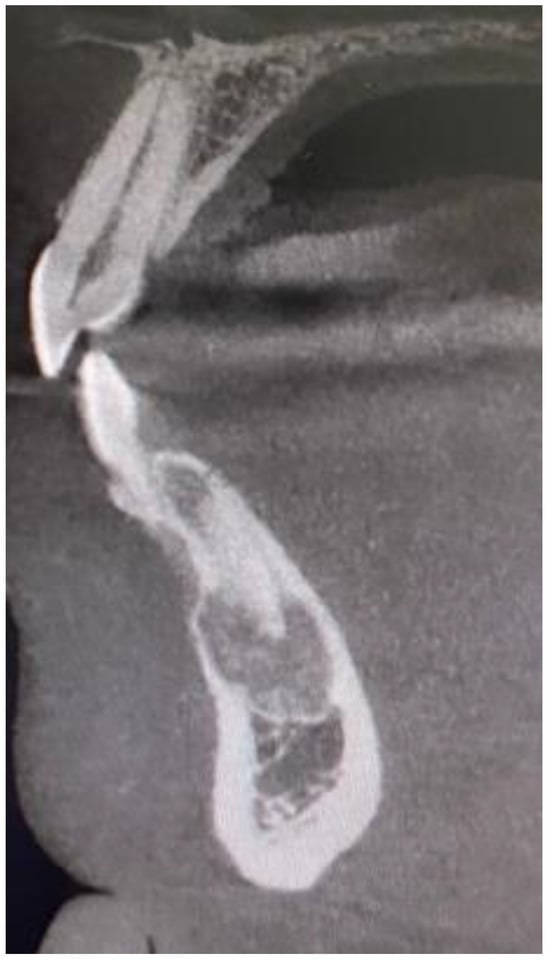

- various stages of calcifying masses inside of the lesion, Figure 5

- may cause cortical expansion or teeth displacement, Figure 5.